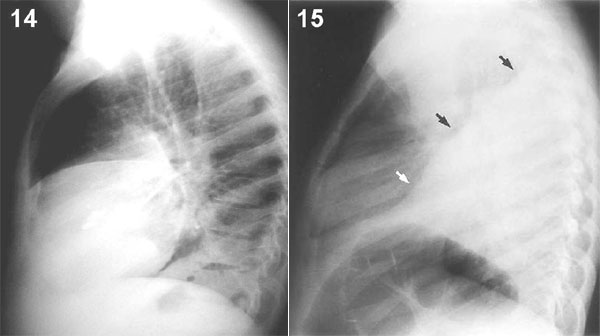

Examine las placas laterales 14 y 15 que corresponden, en el mismo orden, a las placas frontales recién vistas. La primera muestra una condensación del lóbulo medio proyectada sobre la sombra cardíaca y la segunda, una condensación que está por detrás del corazón ocupando todo el lóbulo inferior izquierdo, lo que permite ver por contraste su límite antero-superior determinado por la cisura oblicua de ese lado.

PLACA 14 ------PLACA 15